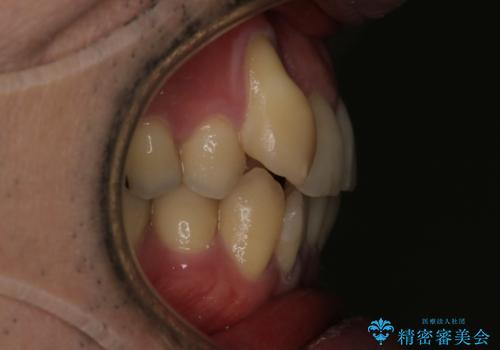

- 右上2番目の歯が舌側転位していることと前歯の叢生(がたつき)を主訴に来院されました。

右上の犬歯が初診時よりかなり歯根露出しており、矯正の力をかけるとさらに歯根露出するリスクがあるため、右上の2番目の歯を前に出すためにも

右上の犬歯を抜歯して歯並びを整える治療計画を立てました。